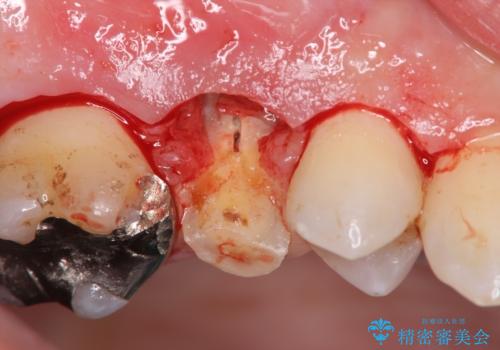

抜歯を行い、咬合機能の回復を行いますが、咬合関係や非常に強い噛み合わせの問題をふまえ、咬合面をメタルにしたメタルボンドブリッジで治療を行うこととしました。

また噛み合わせが深くブリッジの強度が十分に確保できないことから、抜歯時に歯周外科を行うことで十分に安定したクラウン装着をできるような処置を行っています。